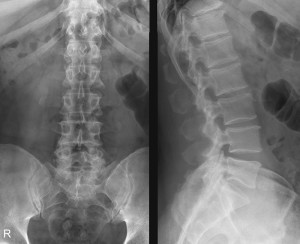

Конечно, нельзя ставить диагноз только лишь на основании таких исследований и наблюдений. В условиях стационара проводятся исследования. Обязательным исследованием является рентгенография поясничного отдела. Снимки выполняются минимум в двух проекциях, боковой и прямой. Еще лучше проводить такую диагностику в трех проекциях, то есть еще в промежуточной. Важную роль играют и более современные методы диагностики, которые считаются полностью достоверными, — ядерный магнитный резонанс и компьютерная томография.